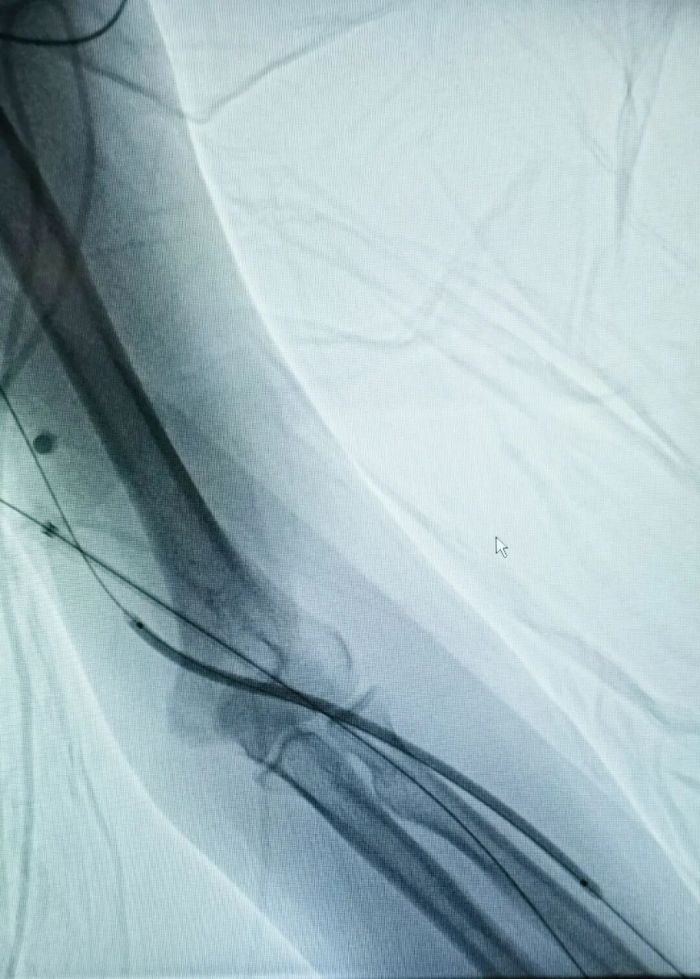

术前.jpg术前影像

术中.jpg

术中影像